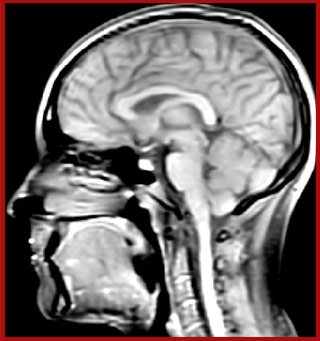

For Dr. Kolind, the Elition excels in advanced neuroimaging for two main reasons. “It's image quality and access to so many different imaging parameters. We’re involved in several multi-center studies, and we can always easily identify the images that came from our Elition scanner, because they are just so beautiful – even though it seems like we’ve set our parameters similarly to other study participants. And as a physicist, being able to do many things, for instance to push resolution and save time, is really helpful.”

Sagittal 3D FLAIR with 0.3 mm3 voxel volume acquired in 5:12 min. using Compressed SENSE showing a (juxta)cortical MS lesion.